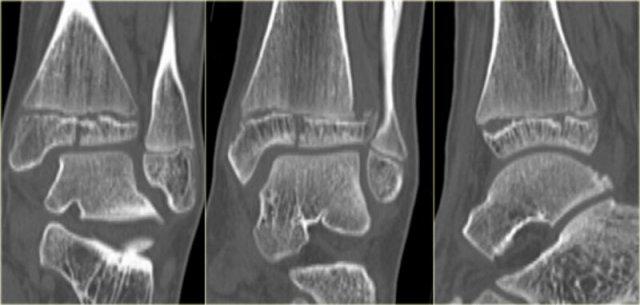

Trong một số trường hợp, gãy mắt cá sau hầu như không nhìn thấy hoặc không thể phát hiện trên phim X-quang và chỉ có thể thấy được trên CT.

Hãy đọc phim X-quang trước, sau đó tiếp tục với hình ảnh CT.

Lưu ý…. có hai đường gãy.

Bạn có thể phóng to hình ảnh bằng cách nhấp vào chúng.

CT cho thấy hình ảnh bong điểm bám tertius tại vị trí bám của dây chằng chày mác sau (mũi tên đỏ).

Sự tương hợp của các mảnh gãy hoàn hảo đến mức không thể nhìn thấy đường gãy trên phim X-quang.

Có thể đường gãy được thấy trên tư thế thẳng (AP) như được chỉ ra bởi các mũi tên đỏ, nhưng điều này còn chưa chắc chắn.

Lưu ý rằng còn có thêm một tổn thương bong điểm bám tại vị trí bám của dây chằng chày mác trước vào xương chày, tức là gãy Tillaux.

Sự kết hợp các dấu hiệu này cho thấy cổ chân không vững.

Cần phải đặt vít cố định khớp chày mác.